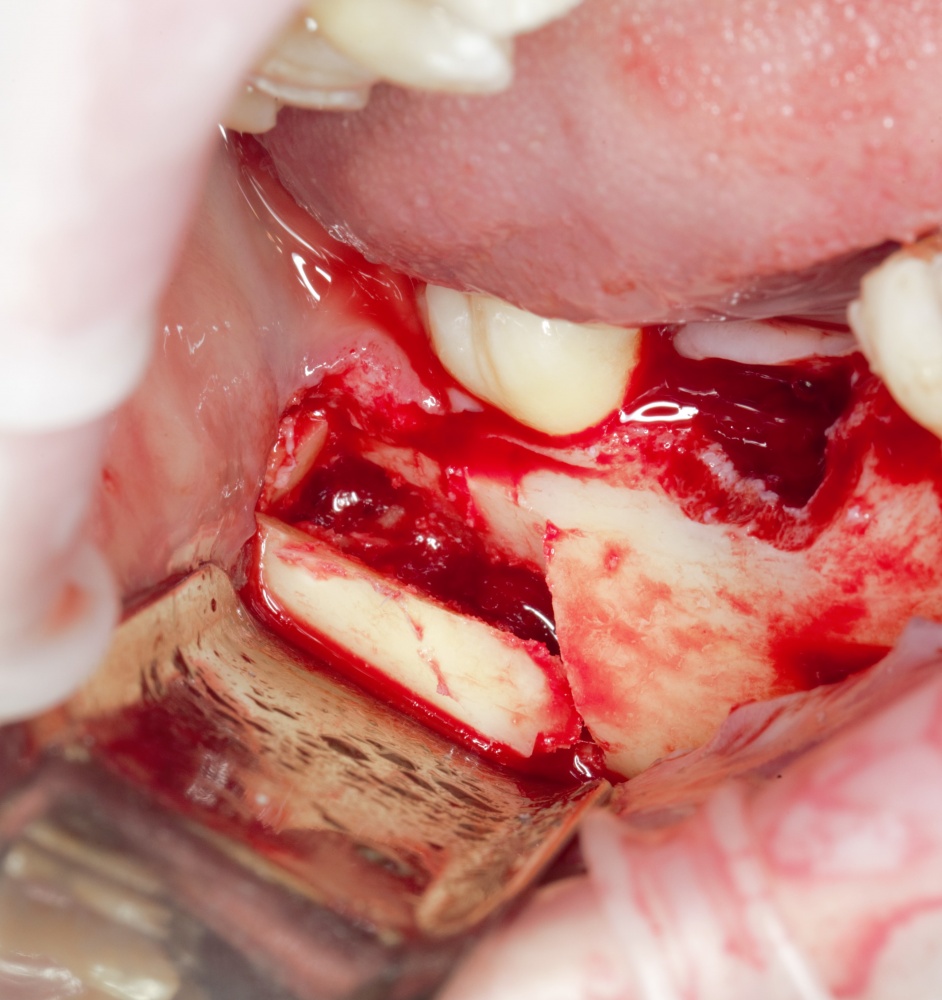

Забор костного фрагмента проводится с наружной косой линии с помощью ультразвукового пьезохирургического инструмента. Ничего сверхнового и супернеобычного тут нет, совершенно стандартная методика. С той лишь разницей, что молоток для этого используют только фашисты и только в гестапо использовать не нужно, всё делается усилием и ловкостью рук.

Нюансы начинаются с обработки принимающего ложа. Да-да, уважаемые друзья, одна из причин некроза блоков, их чрезмерной атрофии и прочих проблем — в отсутствии обработки принимающего ложа. Некоторые делают дырки, но правильнее и эффективнее поступить так:

то есть, просто снять слой кортикальной пластинки с участка, к которому будет фиксироваться костный блок. Почему? Читайте здесь>>.